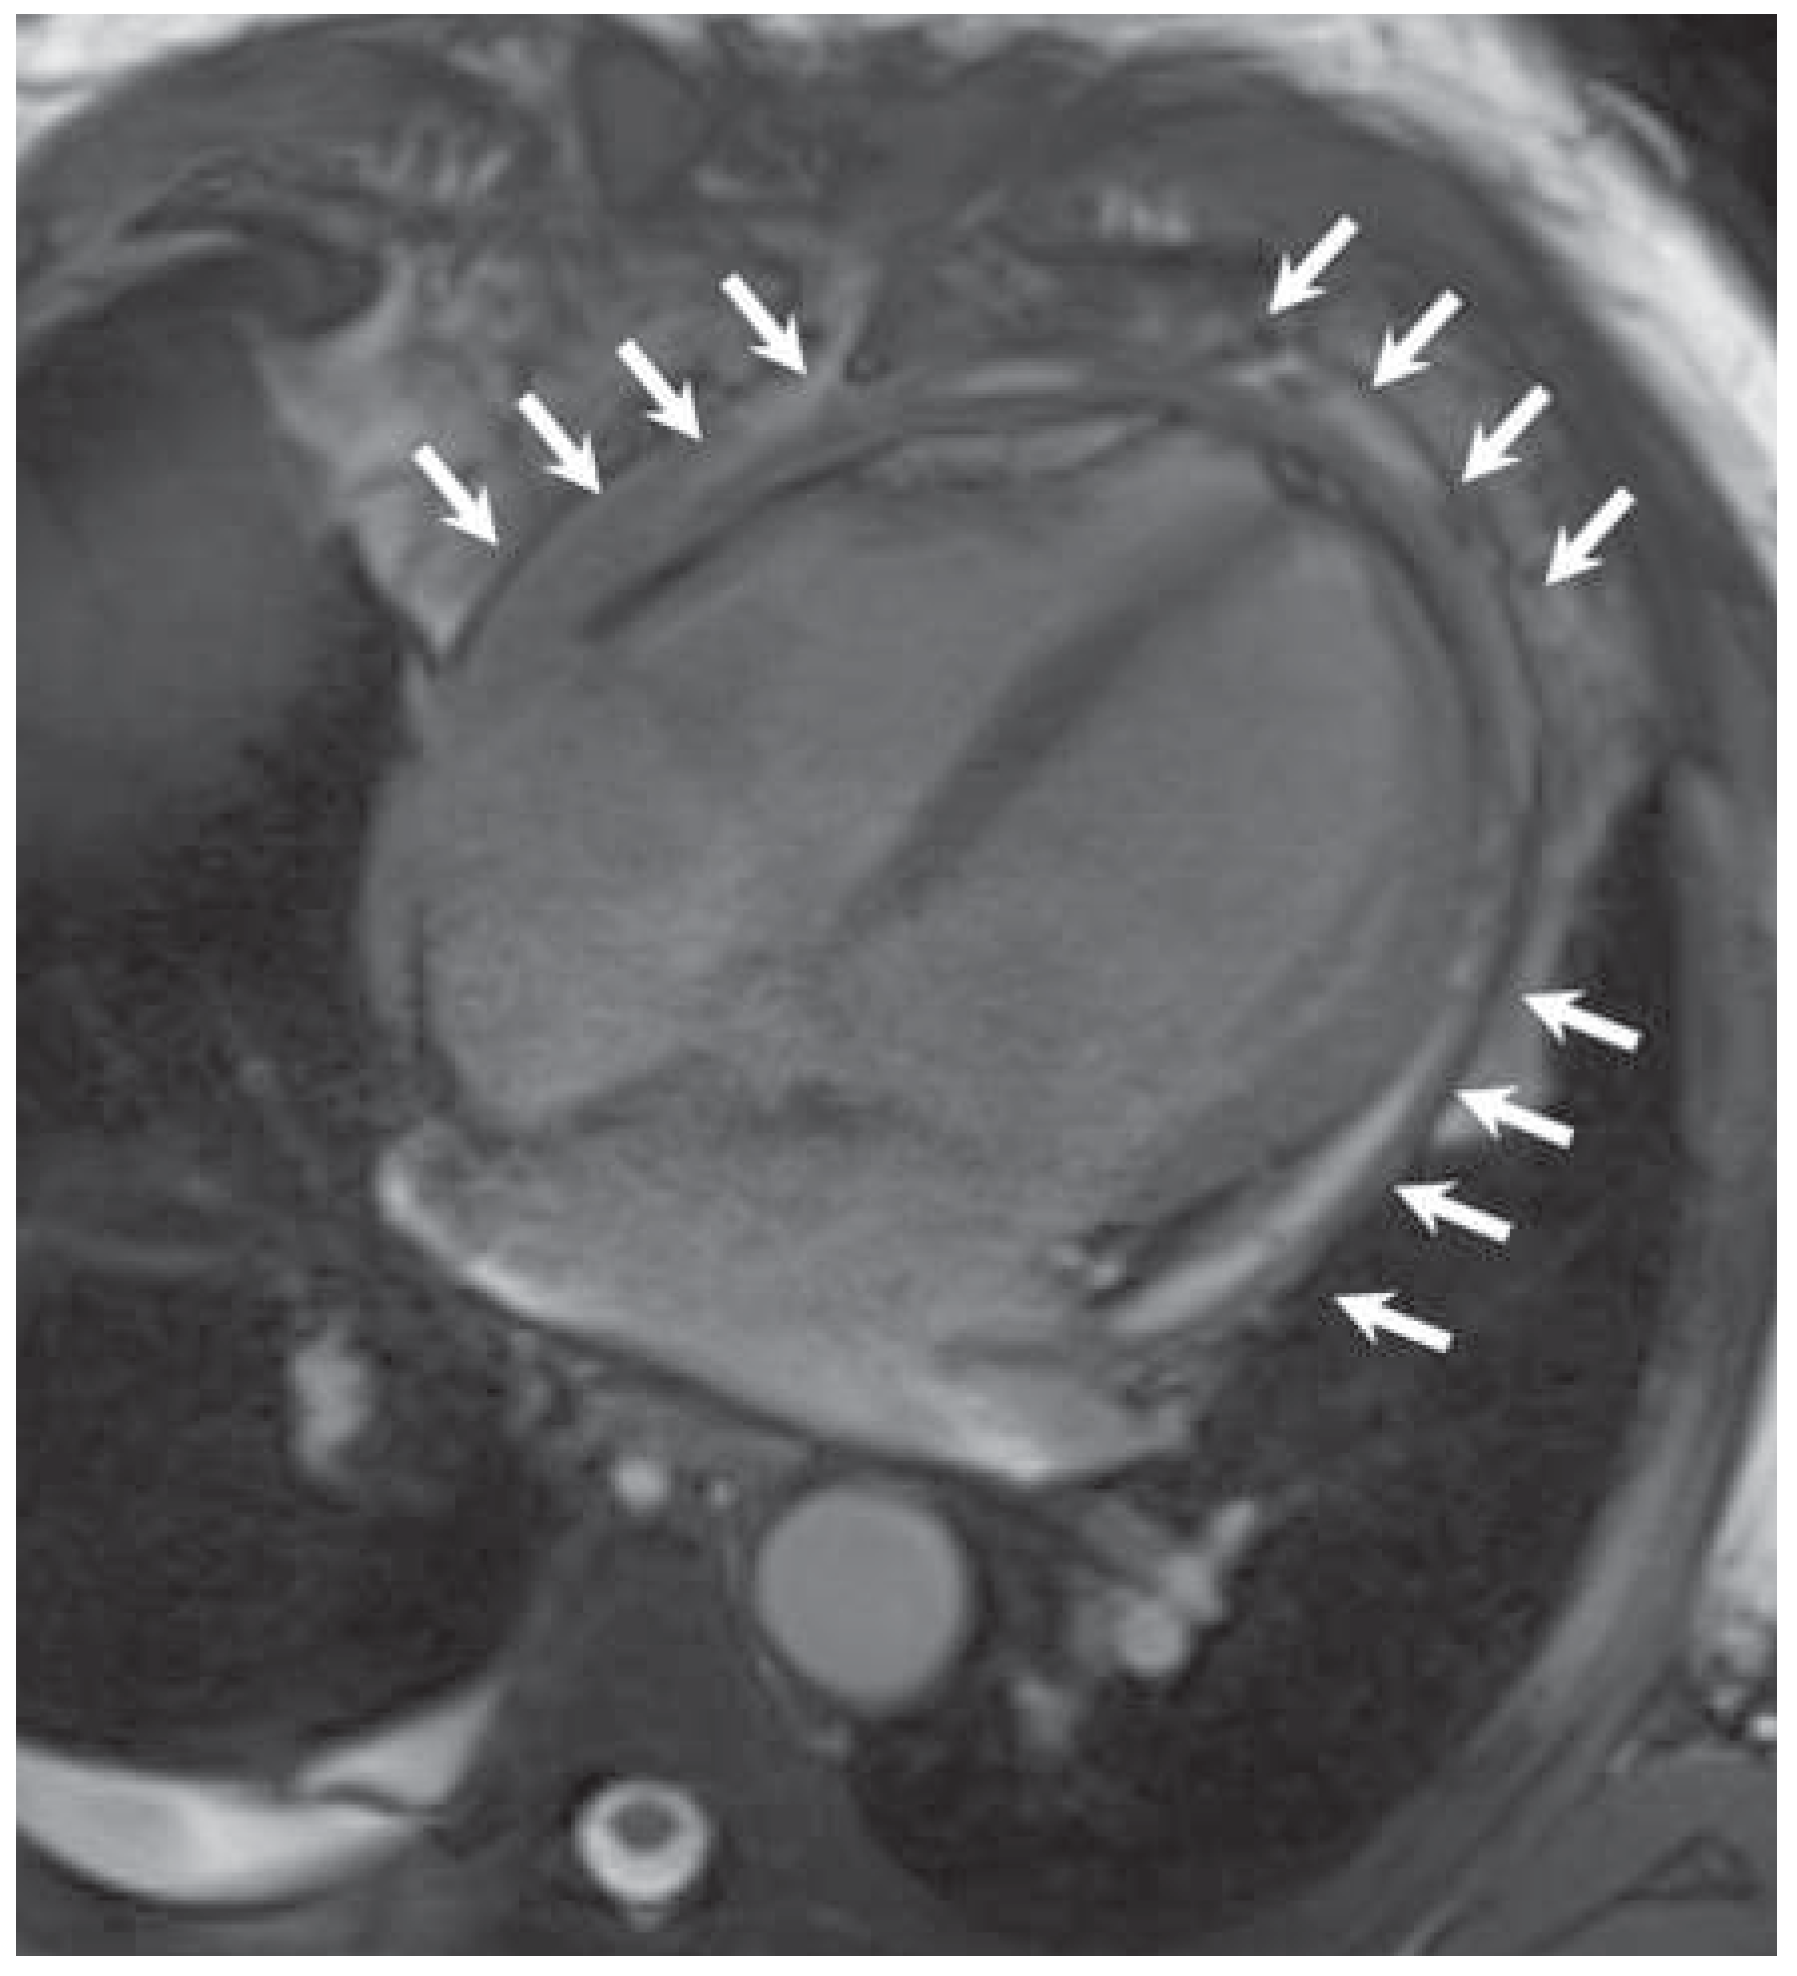

Kussmaul's Sign in Effusive Constrictive Pericarditis